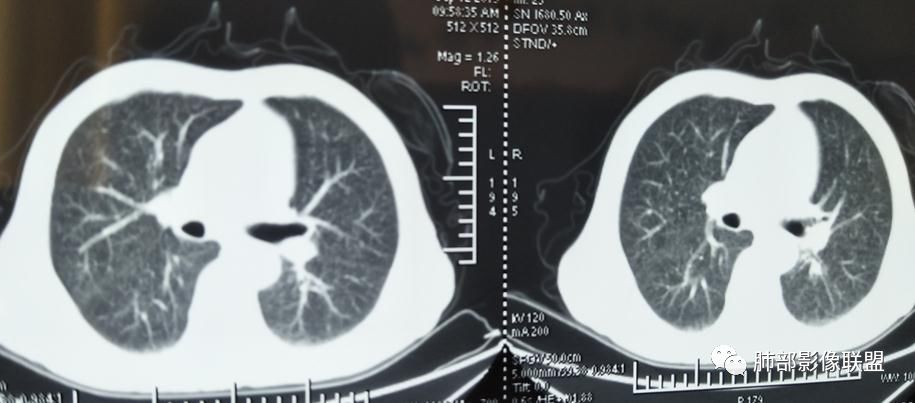

2019年9月12日CT(外院片,手机拍摄)

9月外院片也有弥漫细小结节